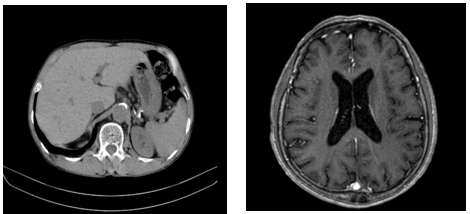

Chụp cắt lớp vi tính ổ bụng: Không thấy bất thường

Chụp cộng hưởng từ sọ não: Thoái hóa myelin chất trắng trên lều (Fazekas 1). Teo não theo tuổi

Hình 2: Hình ảnh chụp cắt lớp vi tính ổ bụng và MRI sọ não: Chưa phát hiện tổn thương thứ phát